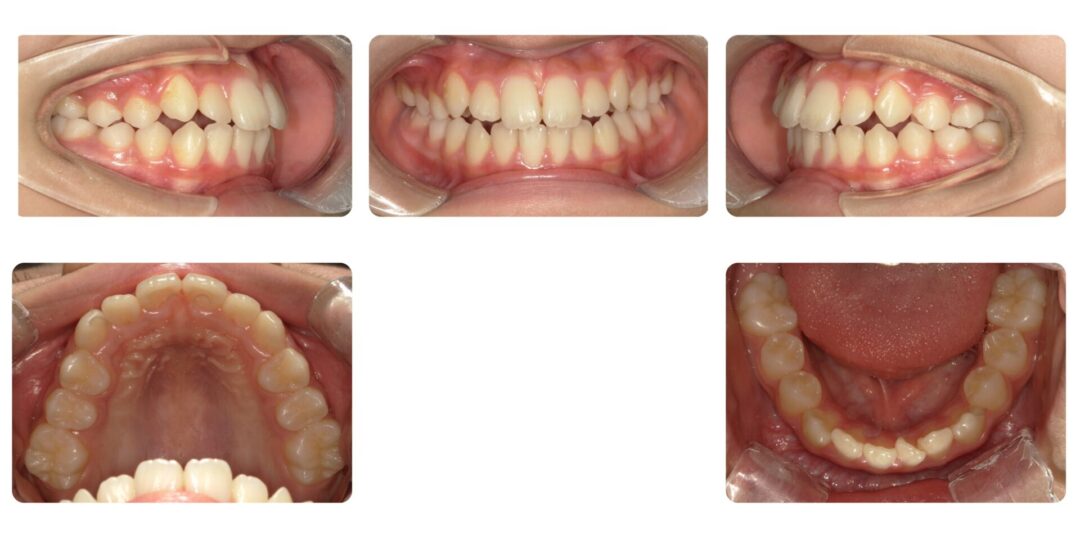

歯槽性上下顎前突|初診時10歳

矯正治療後

治療内容

第一期治療 上顎タングガード付き拡大床による歯列矯正

治療期間

1年4ヶ月